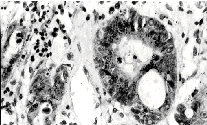

Резко выраженная стромальная экспрессия тенасцина была обнаружена во всех 35 случаях метастатических опухолей легких, однако у разных гистологических вариантов имелись значительные отличия в распределении тенасцин-позитивного материала. В 18 случаях метастазирования плоскоклеточного рака тенасцин-позитивные волокна формировали крупные септы, разделяющие опухоль на отдельные дольки; в толще последних выявлялись волокна, тесно связанные с септами и оплетающие отдельные клетки. В метастазах мелкоклеточного рака [7] и аденокарцином легкого [10] скоплений тенасцина в виде септ не наблюдалось, его стромальная экспрессия в этих опухолях была представлена сетью рыхло расположенных тонких волокон, оплетающих отдельные клетки и имеющих тесную связь с окрашенными стенками сосудов. Внутриклеточная экспрессия тенасцина была верифицирована во всех 18 случаях метастазирования плоскоклеточного рака (рис., а), в 2 случаях метастазирования мелкоклеточного рака (рис., б) и в 8 случаях метастазирования аденокарцином (рис., в). В случае плоскоклеточного рака тенасцин-позитивные клетки обычно распределялись по периферии долек и контактировали с волокнами септ, в случае мелкоклеточного рака и аденокарцином подобной ориентации окрашенных клеток не наблюдалось.

Стромальная экспрессия тенасцина в виде густой сети тонких волокон была обнаружена во всех 18 случаях метастазирования меланом кожи. В 9 метастатических меланомах выявлялись также скопления клеток с диффузной цитоплазматической экспрессией тенасцина (рис., г).

Рис. Особенности экспрессии тенасцина в различных метастатических опухолях головного мозга:

а - плоскоклеточный рак легкого ( 400), б - аденокарцинома легкого ( 400), в - мелкоклеточный рак легкого ( 400), г - меланома ( 200), д - рак молочной железы ( 200), е - рак толстой кишки ( 400).

Во всех случаях окраска ПАП-методом

В 12 случаях метастазирования аденокарцином молочной железы экспрессия тенасцина верифицировалась исключительно в строме опухоли, при этом окрашивались многочисленные тонкие волокна, формирующие крупные междольковые септы (рис. 1, д). Внутри долек и в цитоплазме клеток экспрессия тенасцина не выявлялась.

В 12 случаях метастазирования светлоклеточного рака почки экспрессия тенасцина обнаруживалась в виде интенсивного окрашивания волокон стромы и базальных мембран. В двух опухолях было также верифицировано цитоплазматическое окрашивание отдельных групп клеток.

В 6 случаях метастазирования аденокарцином ЖКТ имела место выраженная внеклеточная экспрессия тенасцина с окрашиванием волокон, базальных мембран и стенок сосудов. Гранулярная цитоплазматическая экспрессия тенасцина выявилась в 3 случаях метастазирования аденокарцином сигмовидной кишки, окрашенные гранулы определялись преимущественно у апикального края клеток (рис. 1, д).